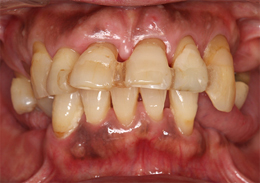

下顎のALL-ON-4①(下の歯のオールオンフォー)

-

- 主訴

- もともと入っているインプラントの周りが腫れ、残りの歯も動いているので力が入らない

- 治療内容

- 下顎右側に以前埋入したインプラントの撤去を行い、歯周病の進行が著しかった残存歯の抜歯を行うと同時にインプラントの埋入を行い、当日仮歯を装着した

- 治療費用

- 下顎ALL-ON-4:4,000,000円(税別)

- 治療期間

- 6ヶ月